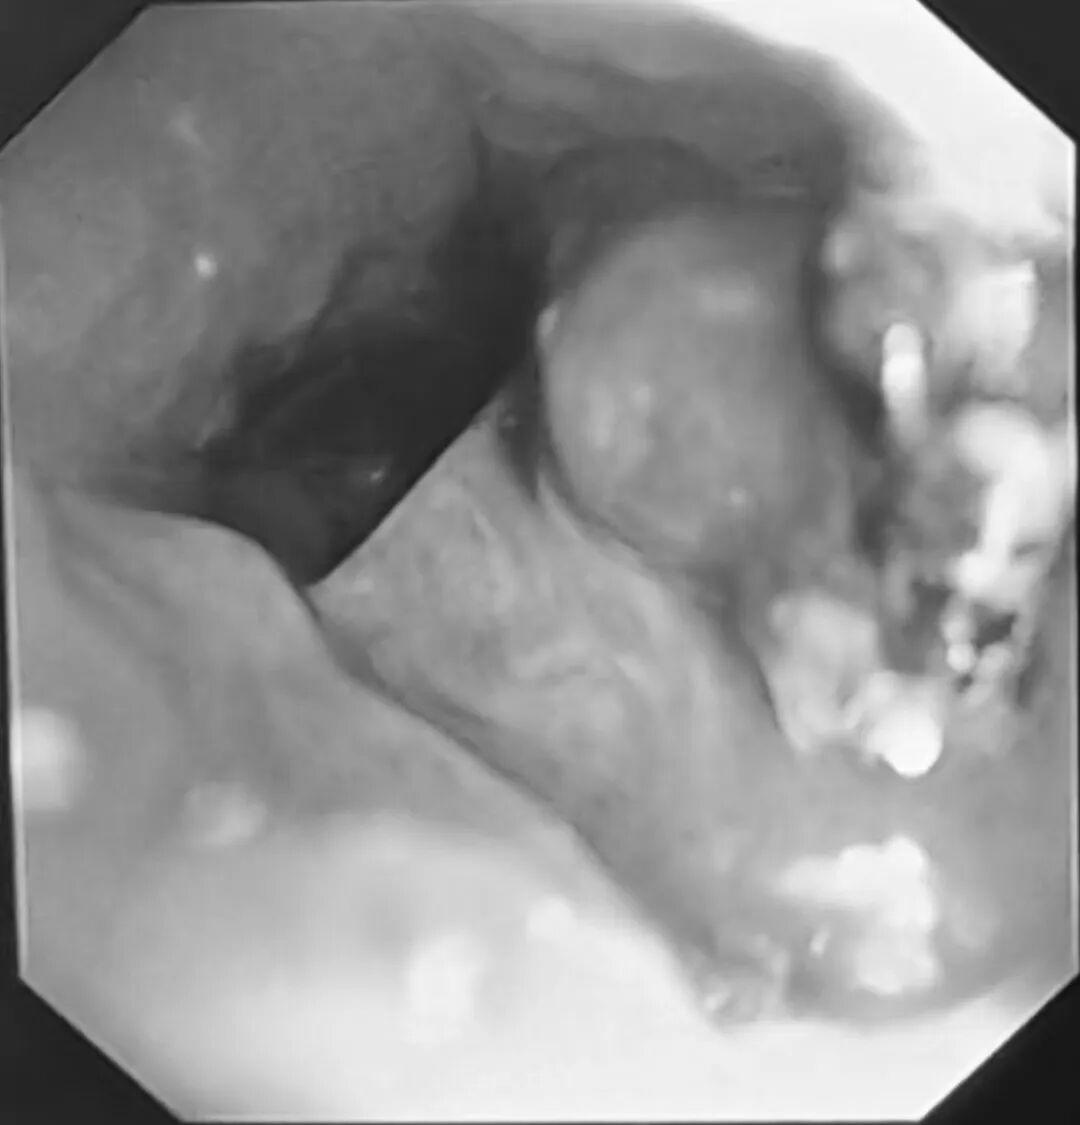

小刘气管插管后,气管镜经过隆突,刚探入右主支气管,屏幕上就出现了异样——大量黄白色脓性分泌物附着在管壁,几乎堵住了视野。王永彬小心操控镜子,一边吸引一边推进,吸除分泌物后,一个被鲜红色肉芽组织紧紧包裹的异物逐渐显露出来,正卡在右上叶支气管开口处,锋利的针头已经深深的嵌入进周围的组织中。

三个月的时间,人体自身的防御机制试图将这个“不速之客”包裹起来。增生的肉芽组织像绳索一样,把图钉牢牢缠住,周围黏膜充血水肿,轻轻一碰就容易出血。